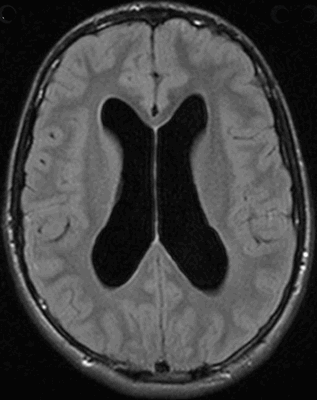

Данная методика дает возможность выявить не только гидроцефалию головного мозга, но и сопутствующие заболевания, точно определить тип патологии. На снимке видны и прямые, и косвенные признаки болезни. К прямым относится увеличение желудочков головного мозга, субарахноидального пространства.

Косвенными признаками являются:

- Величина межжелудочкового индекса от 0,5 и больше;

- Смещение гипоталамуса книзу;

- Отек при напряженной водянке;

- Частичное выпячивание верхней части боковых желудочков.

Исходя из результатов исследования, ставится диагноз и назначается лечение. МРТ может показать заместительную гидроцефалию. Это означает, что в субарахноидальном пространстве присутствует определенное количество жидкости, однако ее наличие является не признаком водянки, а проявлением компенсаторного механизма, связанного с возрастными либо органическими изменениями тканей.